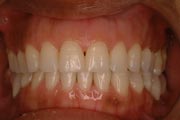

Crowding

After